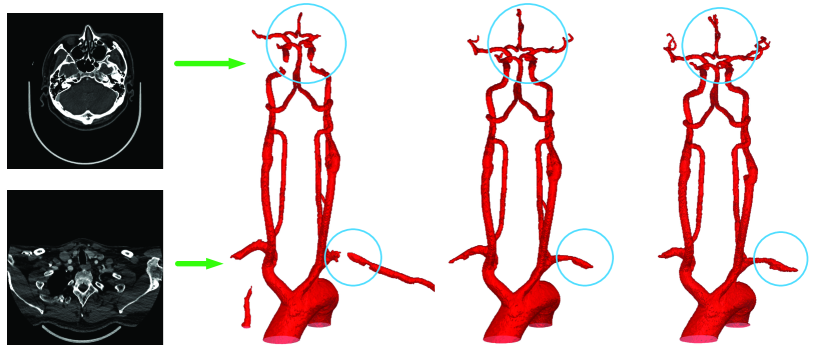

Results on 3MA database: Fig. 5 shows two CTA transverse scans in the 3MA database, the results obtained by using U-Net and our PC-Net, and the ground truth. It reveals that the proposed PC-Net predicts more correct objects in 3D vessel segmentation. Specifically, our PC-Net can extract most of intracranial vessels and does not over-segment many thick vessels (highlighted in blue circles).

Refer to caption

Figure 5: Two CTA transverse scans in the 3MA database (1st column), the segmented results obtained by using U-Net (2nd column) and our proposed PC-Net (3rd column), and ground truth (4th column)